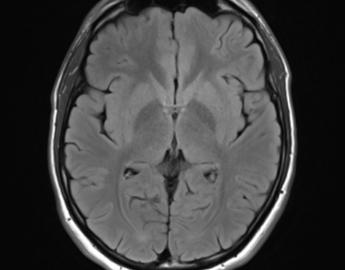

Our lab uses different structural and functional imaging techniques to explore these relationships.